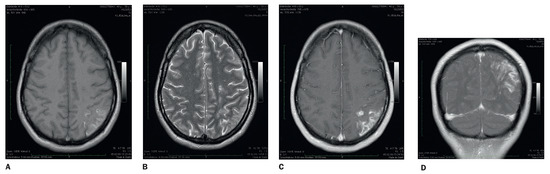

Koinzidenz von ischämischer Enzephalopathie und essentieller Thrombozythämie: zerebrale kortikale Venenthrombose?

Coincidence of ischaemic encephalopathy and essential thrombocytaemia: cerebral cortical vein thrombosis? We here report a 39-year-old women with an ischaemic encephalopathy in temporal association with the first diagnosis of an essential thrombocythaemia. Diagnosis was difficult due to cognitive impairment, a long lasting period [...] Read more.

Coincidence of ischaemic encephalopathy and essential thrombocytaemia: cerebral cortical vein thrombosis? We here report a 39-year-old women with an ischaemic encephalopathy in temporal association with the first diagnosis of an essential thrombocythaemia. Diagnosis was difficult due to cognitive impairment, a long lasting period of progressive symptoms, a former febrile infection, relevant weight loss and ambiguous findings in brain imaging. Meningeal and brain biopsy obtained the diagnosis of an ischaemic encephalopathy and reliably delineated this finding from an infectious or malignant disease of the brain. According to the persistent thrombocytosis subsequent bone marrow biopsy revealed a JAK-2 positive essential thrombocytosis. In the absence of any other pathology we suspected a subacute cortical vein thrombosis as the most likely cause of the ischaemic encephalopathy triggered by the underlying essential thrombocythaemia. After initial anticoagulation she was therefore treated with aspirin for prophylaxis of further vascular events and hydroxyurea for cytoreduction. Follow up examination revealed good recovery from neurological symptoms. Full article